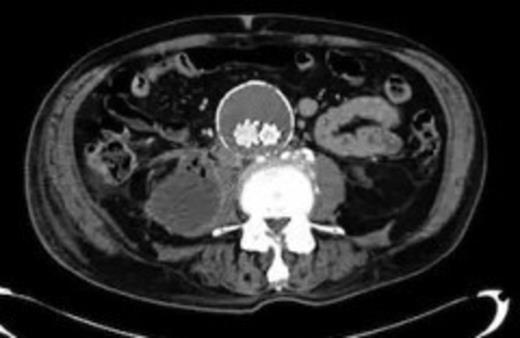

Four weeks following discharge the patient was re-admitted with feeling increasingly unwell, recurrent pyrexia, loss of appetite and mild shortness of breath on exertion. Physical examination was unremarkable except for a temperature of 38.3 centigrade. Blood tests on admission showed Hb 11.4 g/dl (11.5-16.0 g/dl), white cell count 13.1×109/L (4-9.2 x 109/L) and CRP 68mg/L (<3 mg/L). Contrast enhanced CT scan (Fig. 2,3) showed a 50 mm maximum retroperitoneal collection situated between the right kidney and the right iliac vessels. It contained a few loculi of gas. A diagnosis of postoperative right psoas abscess was made. The patient was started on intravenous broad spectrum antibiotics – Tazocin (Piperacillin+ Tazobactam) and Metronidazole. CT guided drainage was carried out using a 10 French gauge pigtail catheter locked pigtail (Meditech Flexima regular all-purpose drainage catheter sets with locking pigtail (Boston Scientific)) (Fig. 4). The isolation of E. coli from the collection with negative Hemocultures suggested a bowel source for the infection but no actual breach was demonstrable. The bowel surgeons ruled out colonic pathology.

A 50 mm maximum retroperitoneal collection situated between the right kidney and the right iliac vessels